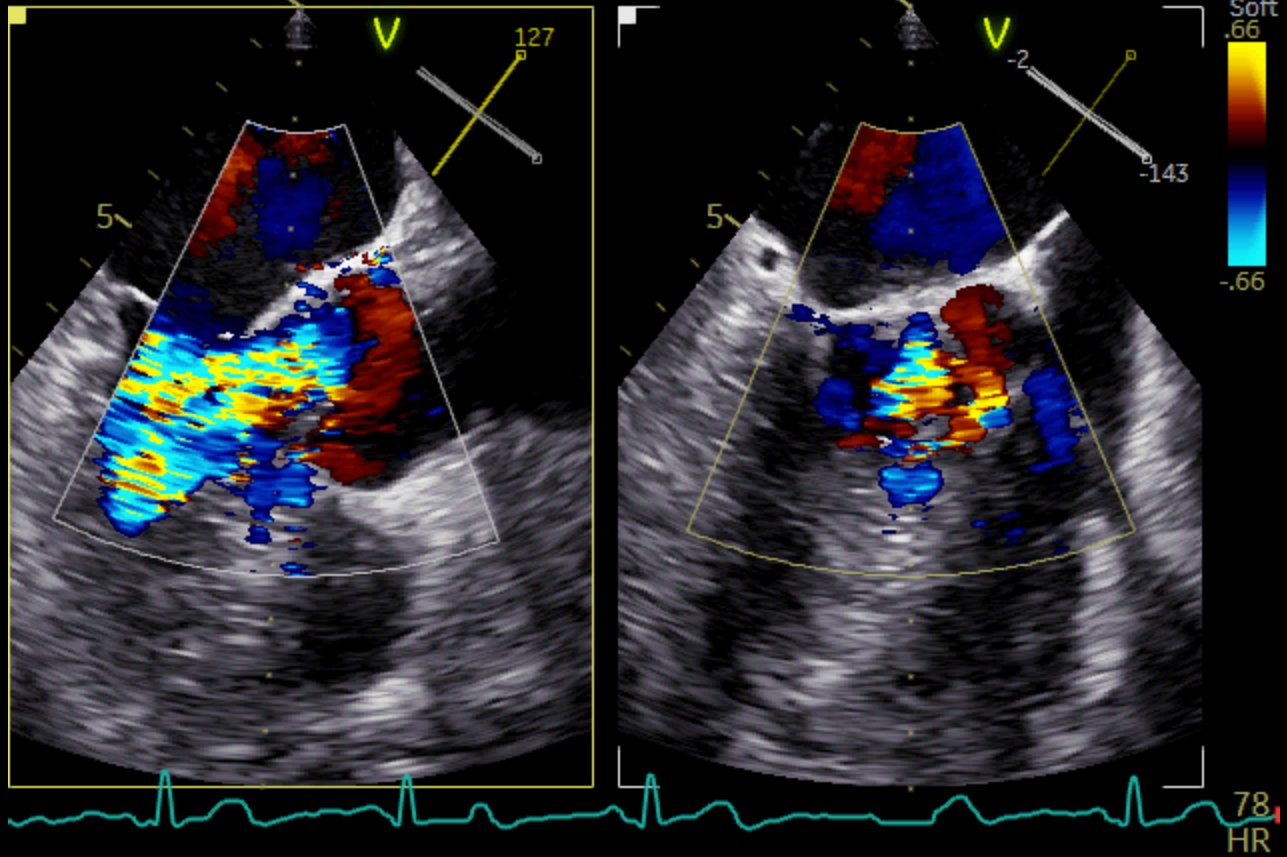

A 51 years-old man presented to the ED for dysarthria and left hemiparesis of sudden onset, dating back to approximately an hour. His past medical history included a deep venous thrombosis, currently under anticoagulant treatment, and a pancreatic cancer with hepatic metastases. Vital signs were normal and the physical examination was unremarkable except for the neurological part. The clinical suspicion of ischaemic stroke due to the occlusion of the internal left carotid artery was promptly confirmed through a CT scan and the patient successfully underwent a mechanical thrombectomy. The following day, to further investigate the nature of his thromboembolism, a TTE was performed: which surprisingly revealed two massive vegetations on the aortic and tricuspid valves. The subsequent TEE showed a circumferential three-cusp aortic involvement with a high-risk 18 mm-filamentous vegetation protruding into the left ventricular outflow tract; severe valvular insufficiency was also detected together with another large vegetation involving the subvalvular tricuspid apparatus. A total body CT-scan highlighted bilateral pulmonary embolism and splenic embolism, as further complications of the endocarditic process. During the stay the patient presented fever and blood exams were consistent with a diagnosis of sepsis; hence, upon the infectious disease specialist advice, he was started on a high-dose-ceftriaxone-and-vancomycin empirical antibiotic therapy. Eventually, blood cultures turned out negative. After a multidisciplinary meeting involving the core of the Endocarditis Team and the hospital oncologists, a conservative approach was chosen over the heart surgery, due to the patient’s critical conditions and poor prognosis. Therefore, he was transferred to the Oncology service to start palliative chemotherapy. Infective Endocarditis is frequently a difficult disease with non-specific systemic symptoms and late diagnosis; however, the onset can also be abrupt, with life-threatening complications, such as our patient’s. Multimodality imaging is key to make a prompt diagnosis of the disease and its complications and to timely plan the therapeutic strategy. A multidisciplinary management through a dedicated Endocarditis Team remains the mainstay to obtain the best clinical outcome.